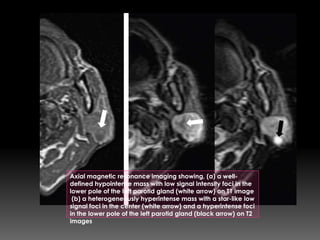

Axial magnetic resonance imaging showing, (a) a well-

defined hypointense mass with low signal intensity foci in the

lower pole of the left parotid gland (white arrow) on T1 image

(b) a heterogeneously hyperintense mass with a star-like low

signal foci in the center (white arrow) and a hyperintense foci

in the lower pole of the left parotid gland (black arrow) on T2

images